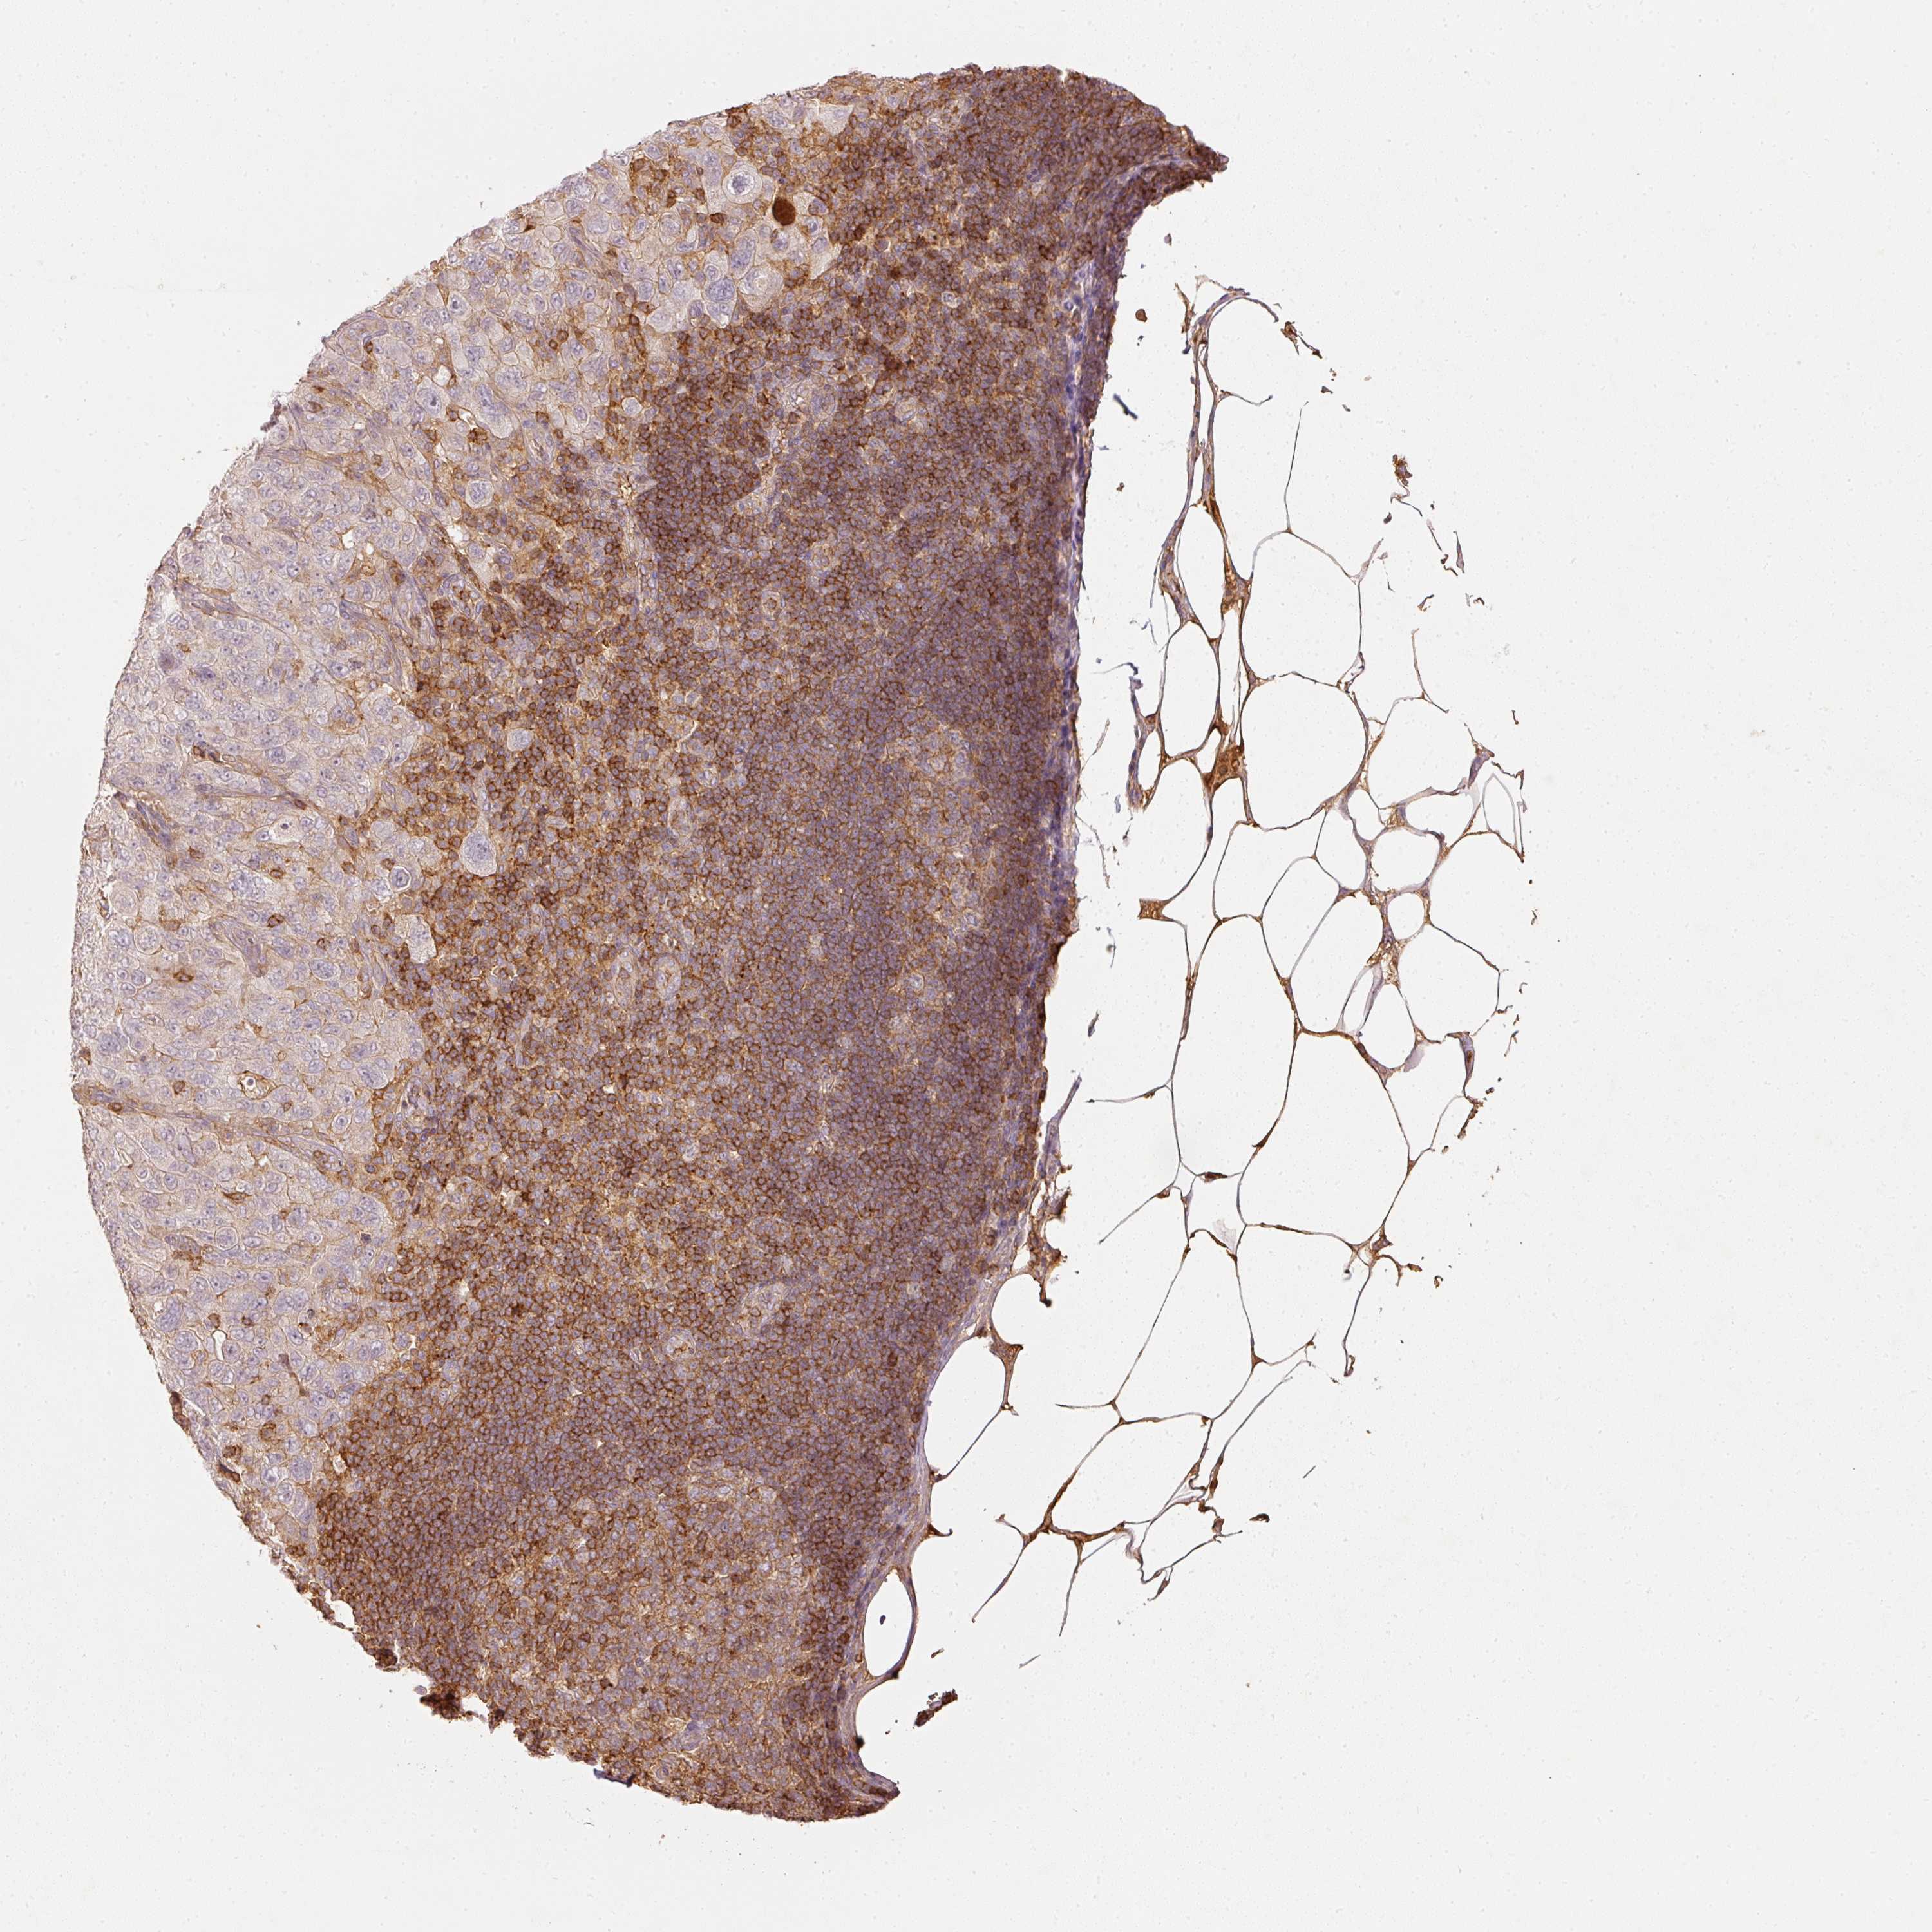

PANCREATIC CANCER - Protein expressioni

A mouse-over function shows sample information and annotation data. Click on an image to view it in a full screen mode. Samples can be filtered based on level of antibody staining by selecting one or several of the following categories: high, medium, low and not detected. The assay and annotation is described here.

Note that samples used for immunohistochemistry by the Human Protein Atlas do not correspond to samples in the TCGA dataset.

Antibody stainingi

Antibody staining in the annotated cell types in the current human tissue is reported as not detected, low, medium, or high, based on conventional immunohistochemistry profiling in selected tissues. This score is based on the combination of the staining intensity and fraction of stained cells.

Each image is clickable and will lead to virtual microscopy that enables deeper exploration of all samples and also displays staining intensity scores, fraction scores and subcellular localization as well as patient and tissue information for each sample.

Antibody HPA018849

Antibody HPA019536

Antibody CAB033987

Staining

High

Medium

Low

Not detected

Intensity

Strong

Moderate

Weak

Negative

Quantity

>75%

75%-25%

<25%

None

Location

Nuclear

Cytoplasmic/membranous

Cytoplasmic/membranous,nuclear

Adenocarcinoma, NOS